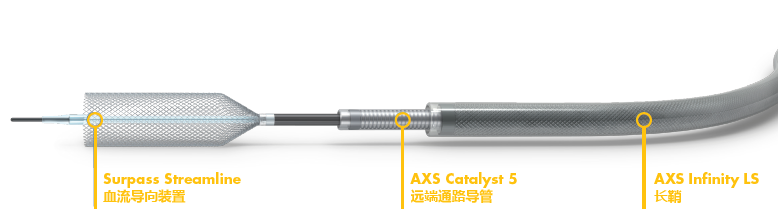

Surpass Streamline

2. 拟单枚Surpass Streamline覆盖长段病变

经Cat5完全释放支架后,拉推送杆后支架近端打开,后将Cat5跟进血流导向装置内尝试“按摩”,支架整体贴壁不够理想。

Cat5通过后海绵窦段狭窄即较前改善

Cat5提供稳定通路,引入3.5mm×10mmHiryu球囊扩张由远端及近端扩张狭窄段及支架贴壁欠佳处

导丝成袢,继续“按摩”改善贴壁

1. Streamline释放后留置导丝,为后续各种操作提供通路,处理更从容;

2. Cat5可轻松跟进到远端,球囊可轻松到位病变;

3. Streamline多网丝且独特的编制方式,径向支撑力较强,是处理此类病变的不错选择;

4. 即使Cat5甚至是长鞘跟进Streamline内,支架也未出现套叠;

5. Streamline可提供的长度更长,支架型号选择简单;

6. Streamline always open,是一款可靠、安全、导流作用明显的“真”血流导向装置。